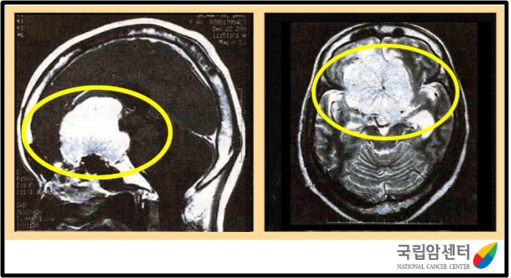

전두엽에 발생한 수막종의 뇌 자기공명영상 사진

2009.12.16